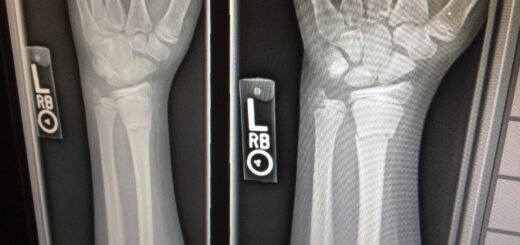

WEEK4 上肢、画像

予習必須。頼むから予習してくれ。実習当日に勉強するのでは遅い。作業も進まない 上肢の続きと、医療画像のはじまり。小テスト。腕神経叢のスケッチの試...